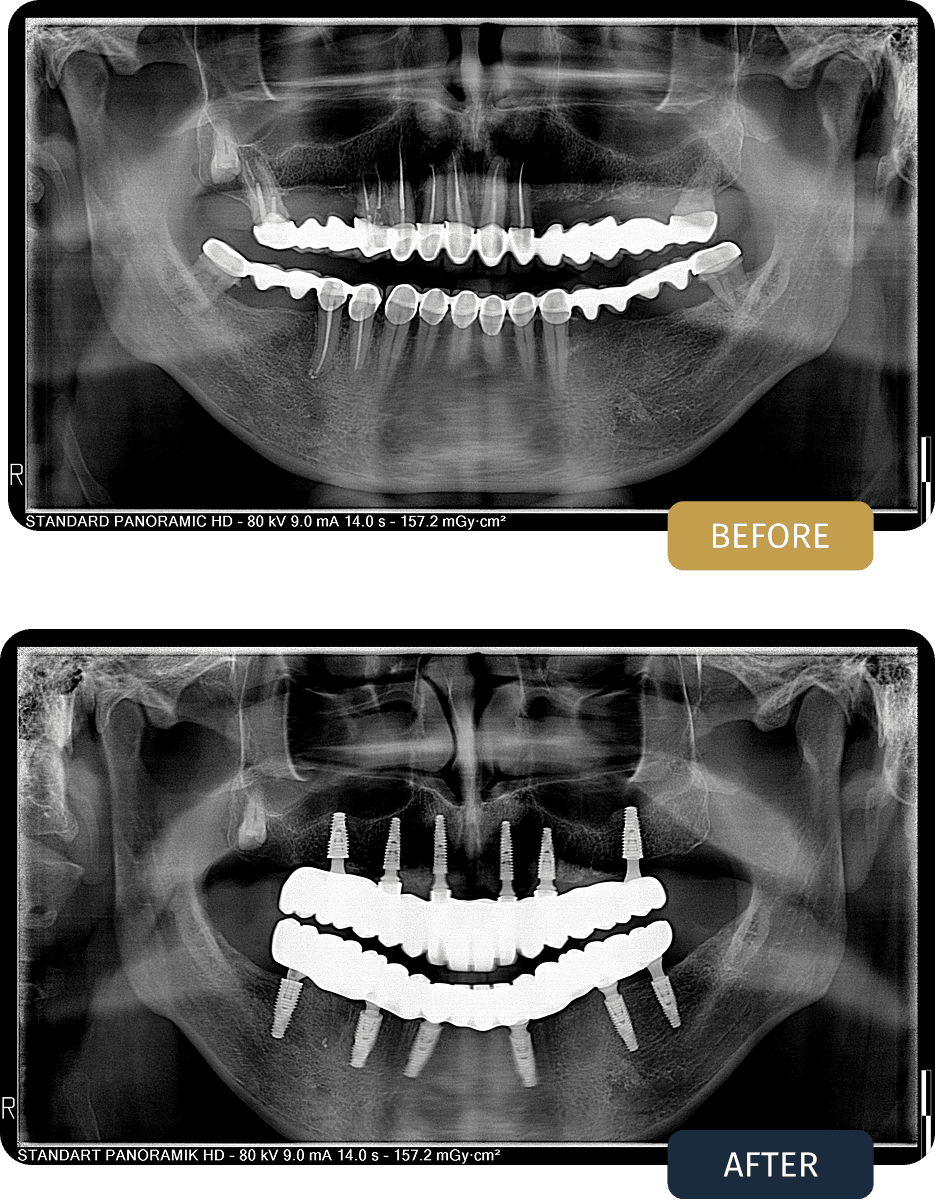

FULL ARCH ALL ON 6 REHABILITATION

Csaba Balogh, 47, from the EU

• Upper Jaw: All on 6 with Fixed Prosthesis

• Lower Jaw: All on 6 with Fixed Prosthesis

A comprehensive full mouth rehabilitation plan was developed using an All on 6 concept for both jaws.

All remaining compromised teeth were removed, and six implants were strategically placed in each jaw to maximise load distribution and prosthetic support.

This approach allowed for the delivery of a fixed, non removable solution designed to replace both teeth and lost support structures, while ensuring long term durability and functional efficiency.

Csaba presented with extensive dental failure across both jaws. Although he had previously received dental crown treatments, these restorations had deteriorated significantly over time and were no longer functional or stable.

Clinical examination and panoramic imaging showed advanced structural compromise, poor long term prognosis of the remaining teeth, and insufficient support to maintain conventional restorations.

Given the condition of the existing teeth and bone structure, a full arch implant solution was indicated for both jaws to restore function and long term stability.

Post treatment panoramic imaging confirmed correct implant positioning and stable integration in both jaws.

The final fixed prostheses restored proper bite alignment, chewing function, and overall oral stability, replacing the previously failed crown restorations with a long term implant supported solution.